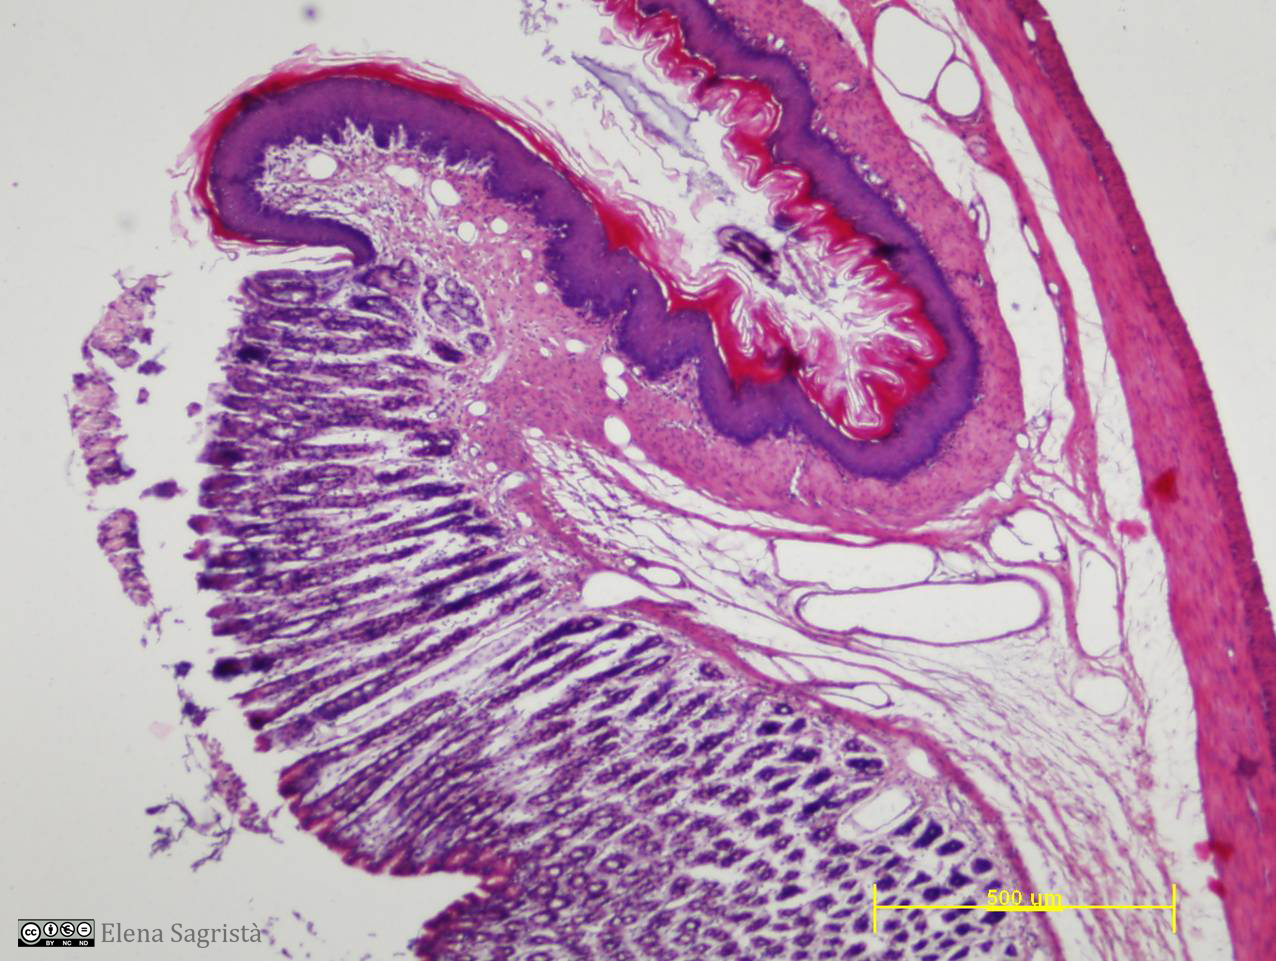

Imatges de preparacions histològiques de teixit epitelial. Microscopia òptica.